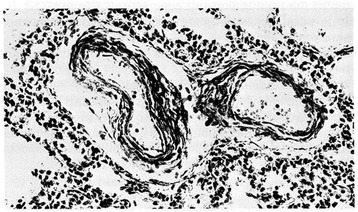

Figure 8.

Pulmonary arteriole from a 11-day-old infant who died from severe perinatal asphyxia. Marked thickening of medial muscle mass is evident (PAS-Gieson stains). From Distefano G et al. [12] Med Surg Ped 1992. (Personal observation).